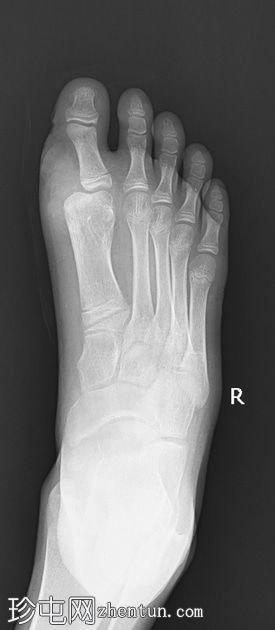

术前

X线片

正位片

侧位片

可见第一趾重复畸形,以第一跖骨为中心,多出的趾位于内侧并呈一定角度,同时伴有第一跖骨增宽。未见其他部位重复畸形。其他可见的骨骼和关节均正常。